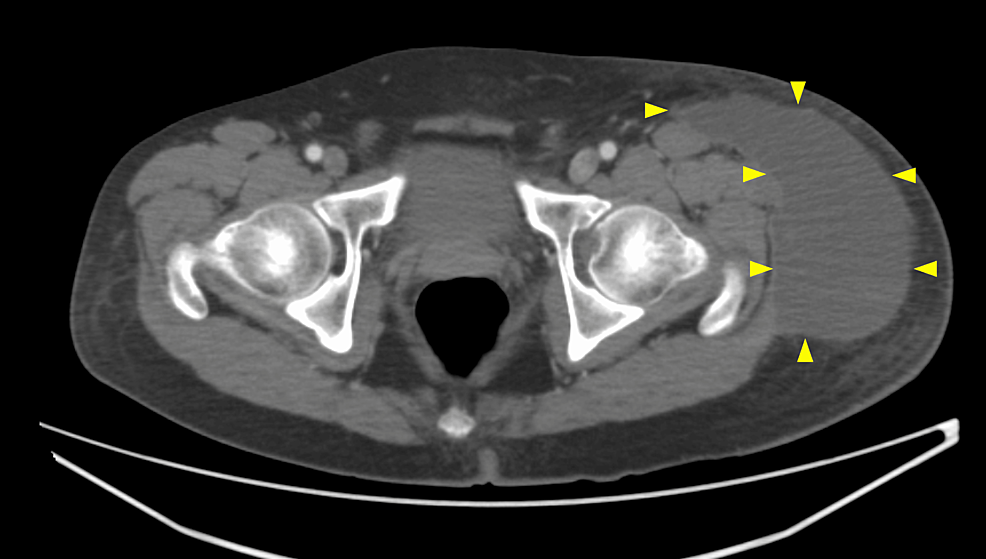

Figure 2 from The MorelLavallée lesion pathophysiology, clinical Morel Lavallee Lesion Rehab it most commonly occurs in the thigh, hip, and pelvis. we aimed to provide a comprehensive overview of mlls to increase awareness of optimum treatment options. Because such lesions are prone to a missed or delayed diagnosis, it may present. surgical interventions such as open debridement, techniques to close dead. the treatment for morel‐lavallée lesion is. Morel Lavallee Lesion Rehab.